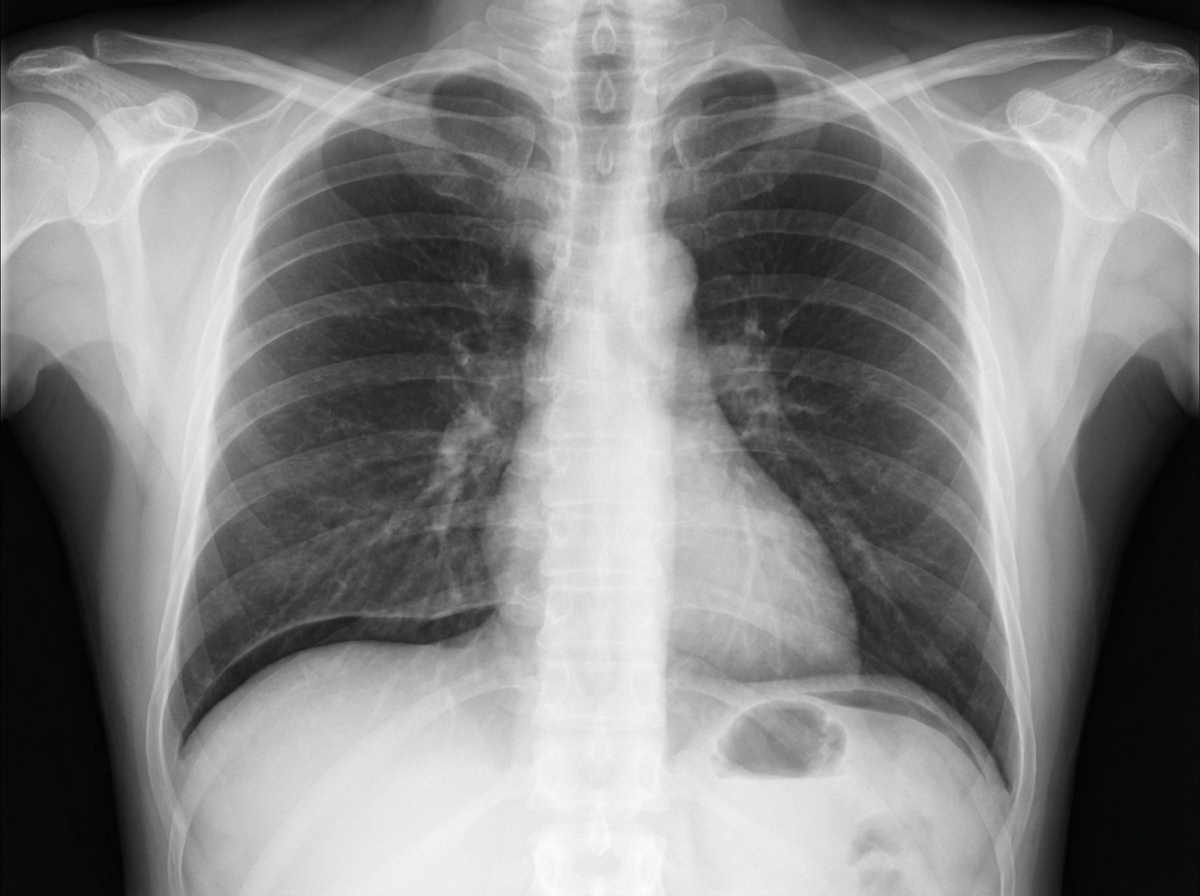

A 54-year-old woman comes to the emergency department because of a 5-hour history of diffuse, severe abdominal pain, nausea, and vomiting. She reports that there is no blood or bile in the vomitus. Two weeks ago, she started having mild aching epigastric pain, which improved with eating. Since then, she has gained 1.4 kg (3 lb). She has a 2-year history of osteoarthritis of both knees, for which she takes ibuprofen. She drinks 1–2 glasses of wine daily. She is lying supine with her knees drawn up and avoids any movement. Her temperature is 38.5°C (101.3°F), pulse is 112/min, respirations are 20/min, and blood pressure is 115/70 mm Hg. Physical examination shows abdominal tenderness and guarding; bowel sounds are decreased. An x-ray of the chest is shown. Which of the following is the most likely cause of this patient's current symptoms?